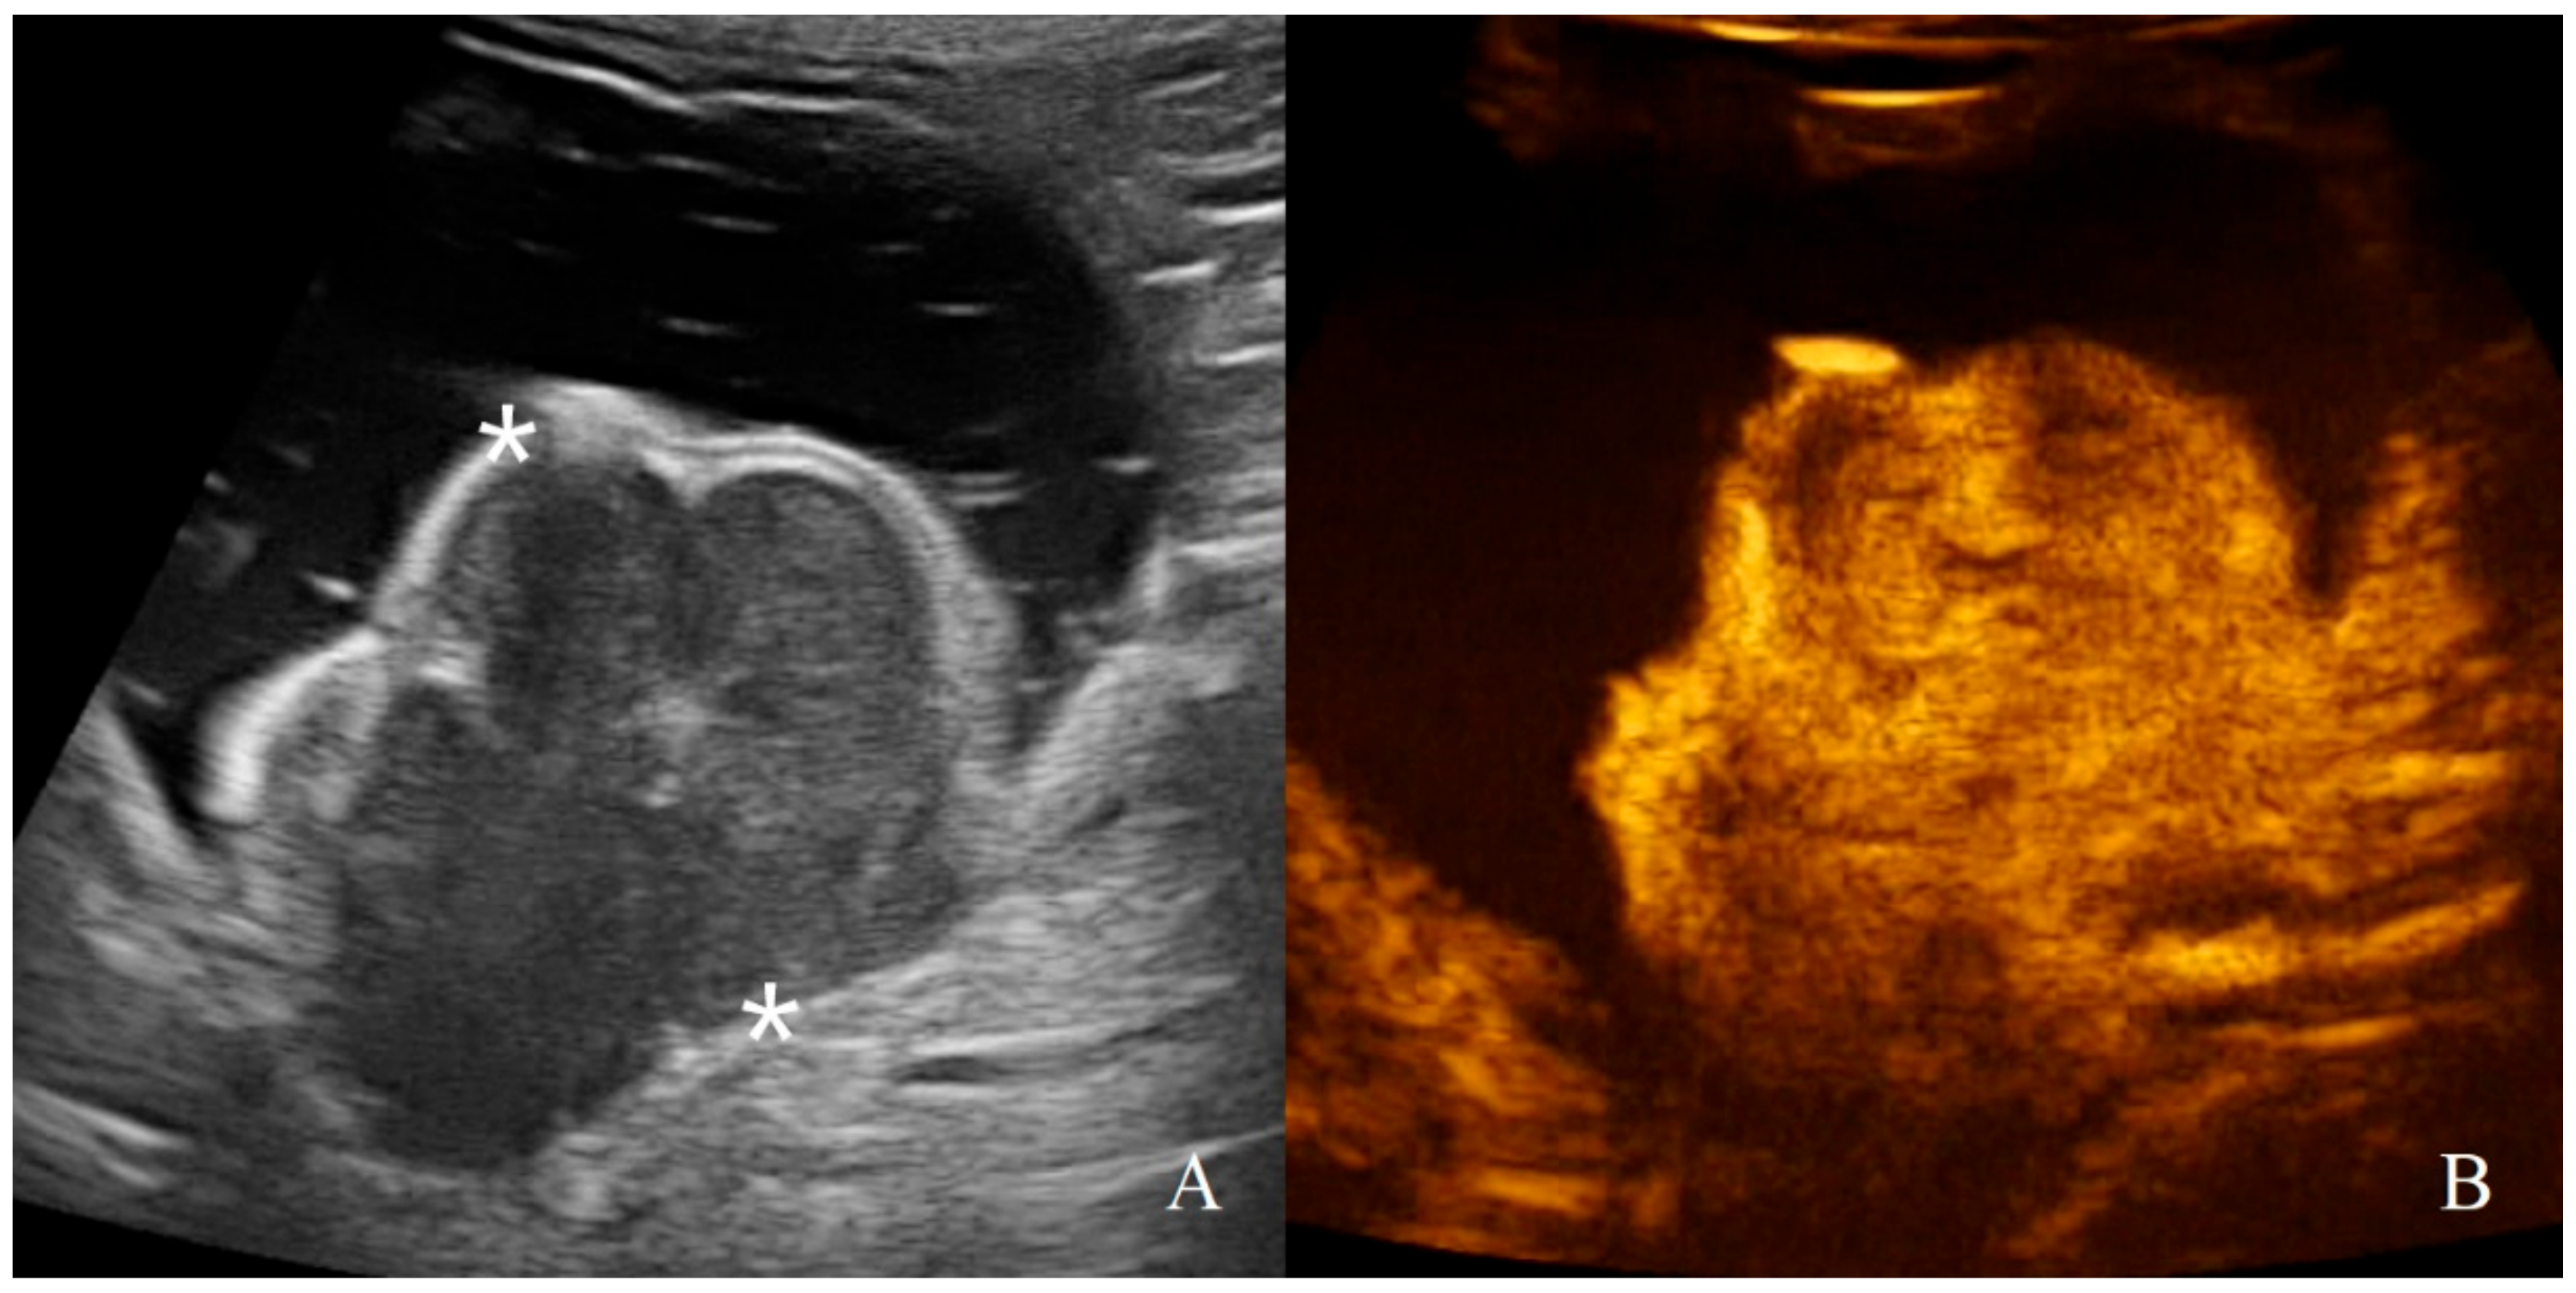

3.2. Analysis of B-Mode Examination

3.3. Analysis of CEUS Examination